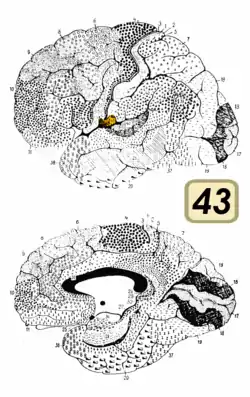

Brodmann area 43, the subcentral area, is a structurally distinct area of the cerebral cortex defined on the basis of cytoarchitecture. Along with Brodmann Area 1, 2, and 3, Brodmann area 43 is a subdivision of the postcentral region of the brain,[1] suggesting a somatosensory ('feeling of the body') function. The histological structure of Area 43 was initially described by Korbinian Brodmann, but it was not labeled on his map of cortical areas.[2]

In the human subcentral area 43, a sub area of the cytoarchitecture is defined in the postcentral region of the cerebral cortex. It occupies the postcentral gyrus, which is between the ventrolateral extreme of the central sulcus and the depth of the lateral sulcus, at the insula. Its rostral and caudal borders are approximated by the anterior subcentral sulcus and the posterior subcentral sulcus, respectively. Cytoarchitecturally, it is bounded rostrally, by the agranular frontal area 6, and caudally, for the most part, by the caudal postcentral area 2 and the supramarginal area 40.[1]